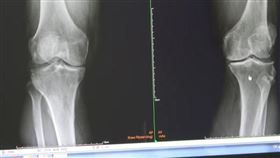

天天站12小時膝蓋磨壞 醫:激烈16蹲也會

台中東勢一名小吃店老闆,每天工作12小時幾乎都站著,...